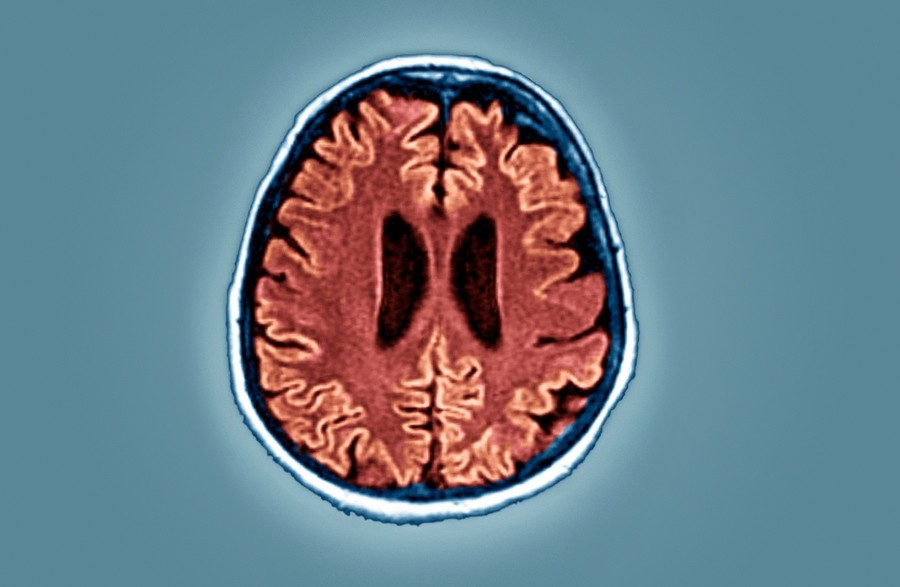

Durch die proteolytische Verarbeitung des Amyloid-Vorläuferproteins und die anschließende Hyperphosphorylierung des Tau-Proteins führt die Alzheimer-Krankheit dazu, dass sich im medialen Temporallappen und in neokortikalen Strukturen, die am stärksten betroffenen Bereiche des Gehirns, Beta-Amyloid-Peptide ansammeln. Dies ist eine der Hauptursachen für eine Reihe von Ereignissen, die zu mitochondrialer Dysfunktion, synaptischer Dysfunktion und oxidativem Stress führen. Akute COVID-19-Infektionen, die zum Tod führen, treten häufiger bei Patienten mit Alzheimer-Krankheit auf.

Durch die fehlerhafte Faltung des Prionproteins bei der Creutzfeldt-Jakob-Krankheit und die Anhäufung von Beta-Amyloid-Peptiden bei der Alzheimer-Krankheit kommt es in beiden Fällen zu einer schwerwiegenden synaptischen Dysfunktion. Dies führt zu einem fortschreitenden Verlust von Nervenzellen und letztendlich zu irreversibler Demenz. Bei der Creutzfeldt-Jakob-Krankheit stehen besonders die Mechanismen im Fokus, durch die pathologische Prionen ihre toxischen Effekte entfalten und sich im Gehirn ablagern.